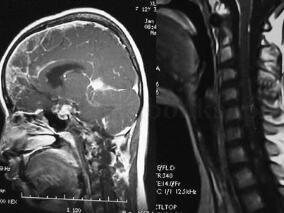

1小时条评论基本资料:患者,女性,50岁,右耳听力渐进性下降伴耳鸣2年余,走路不稳1年,右侧牙痛伴面部麻木、肌肉阵发性抽搐2周余。体检:音叉试验显示右耳感音神经性听力下降。右侧面部感觉减退,角膜反射减退。 问题: 1﹒初步诊断考虑哪些疾病?有哪些依据? 2﹒需要补充...